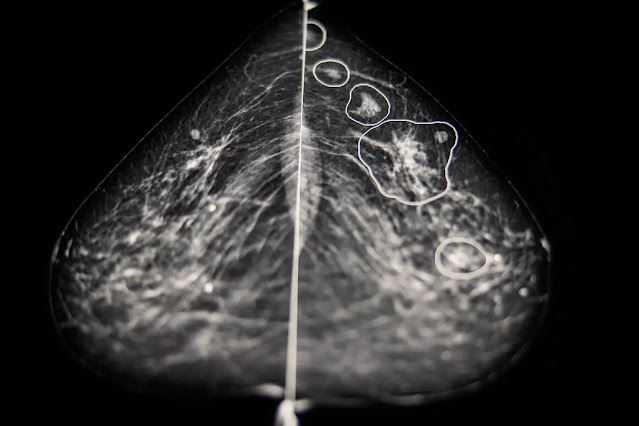

يمكن الآن استخدام تقنية الذكاء الاصطناعي (AI) للكشف عن سرطان الثدي في المستقبل القريب وتم العثور على هذه التقنية لتكون فعالة وإن لم تكن أكثر من أخصائي الأشعة البشرية في تحديد سرطان الثدي في 250000 عملية مسح بالأشعة في دراسة نشرت العام الماضي وكان أيضًا قادرًا على قراءة النسخ الممسوحة ضوئيًا بسرعة أكبر بشكل عام ويتم حاليًا اختبار أنظمة الذكاء الاصطناعي التي تحلل صور الثدي الشعاعية وتستخدم التعلم الآلي لتحديد حالات سرطان الثدي المحتملة بدقة أكبر من أطباء الأشعة البشرية.

ويمكن أن تساعد هذه التقنية الأطباء في اكتشاف سرطان الثدي وأنواع أخرى من السرطانات في وقت مبكر وعلاج المرضى بشكل أكثر فعالية ووفقًا للدراسة يمكن أن يؤدي دمج التقنيات في المجال الطبي إلى تقليل عبء العمل على اختصاصي الأشعة من خلال توفير نظام آلي يمكنه تقديم رأي ثانٍ بسرعة وبدقة وتعمل الشركات على مثل هذه البرامج لسنوات حيث أصبحت تقنيات الذكاء الاصطناعي الحالية أكثر قدرة على أداء مهام أكثر تعقيدًا.

وذكرت Insider سابقًا عن برامج Google التي كانت قادرة على التفوق على الأطباء أثناء التطوير في عام 2020 وكما زعمت أن برنامج الذكاء الاصطناعي المصمم للعمل كقارئ ثانٍ بعد تحليل الإنسان للفحص تفوق على محترفي الرعاية الصحية وقلل أعباء العمل بنسبة 30٪ على الأقل وفي الوقت نفسه ساعد الذكاء الاصطناعي في تقليل عبء العمل على العاملين في مجال الرعاية الصحية وذكرت الصحيفة أن نجاح التكنولوجيا أدى إلى اعتمادها في عدد من الدول الأوروبية.

وتقوم بعض العيادات والمستشفيات في الولايات المتحدة أيضًا بتجربة استخدامه وتدعم النتائج الأبحاث السابقة التي توصلت إلى نتائج متسقة للذكاء الاصطناعي في اكتشاف السرطانات وتقليل الإيجابيات الكاذبة والسلبيات الكاذبة ولا يزال الاستخدام الواسع لتقنية الكشف عن السرطان يواجه العديد من العقبات ولا يزال الأطباء والذكاء الاصطناعيون يواجهون العديد من العقبات ويأمل المطورون تخطي هذه العقبات والبدء في إستخدام هذه التقنيان بأسرع وقت ممكن.

وبالإمكان اعتماد الأنظمة على نطاق واسع كقارئ ثانٍ أو ثالث لشاشات سرطان الثدي بما يتجاوز العدد المحدود للأماكن التي تستخدم هذه التقنية الان ولكن قبل أن يصبح هناك حاجة إلى تجارب إكلينيكية إضافية ويجب أن تُظهر الأداة أنها يمكن أن تنتج النتائج الدقيقة عن النساء من جميع الأعراق والأعمار وأنواع الجسم حيث قال أطباء الأشعة : إن التكنولوجيا يجب أن تثبت قدرتها في التعرف على الأشكال الأكثر تعقيدًا من السرطانات وتقليل الإيجابيات الكاذبة.

وأثارت أدوات الذكاء الإصطناعي نقاشًا حول ما إذا كانت سوف تحل محل اختصاصي الأشعة البشرية ومع مواجهة صانعي التكنولوجيا للتدقيق التنظيمي والمقاومة من بعض الأطباء والمؤسسات الصحية في الوقت الحالي بدو هذه المخاوف مبالغًا فيها حيث يقول العديد من الخبراء إن التكنولوجيا سوف تكون فعالة وموثوقة من قبل المرضى فقط إذا تم استخدامها بالشراكة مع أطباء مدربين على هذه التقنيات التي تستخدم الذكاء الإصطناعي.